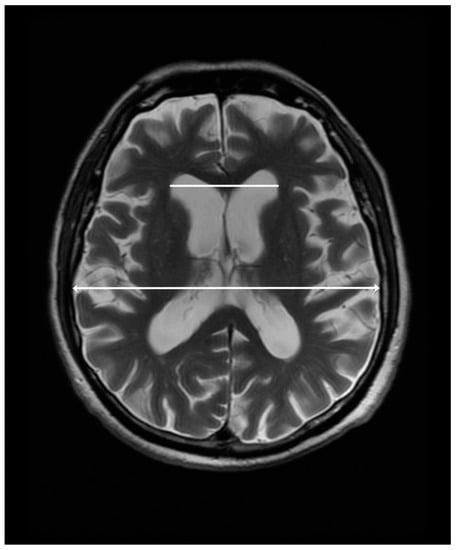

The measurement of the maximum width of the frontal horns (FH) and Evans’ Index (EI) was taken in the axial images parallel to the anterior-commisure–posterior-commisure plane in T2-weighted sequences. We calculated the Evans Index by dividing the maximal right-to-left width of the frontal horns of the lateral ventricles by the maximal inner diameter of the skull at the same level. Figure 1 illustrates the method of measurement of the above-mentioned parameters.

Figure 1.

The measurement of the maximal right-to-left width of the frontal horns of the lateral ventricles (48 mm, white line) and the maximal inner diameter of the skull (137 mm, white line with arrowheads) in a 77-year-old male with a clinical diagnosis of PSP. The Evans Index is 0.35 for this patient.